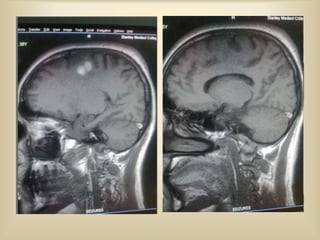

MRI BRAIN REPORT

 MRI brain shows T1 hyperintense / non

suppressible T2 hyperintensity in the right

high parietal lobe. The lesion shows

peripheral blooming in T2 gradient sequence

suggestive of hemorrhage.

 Absence of flow voids in mid sagittal and

transverse sinus in FLAIR images suggestive

of sinus thrombosis

 T1 hyperintensity noted in superior sagittal

sinus and right transverse sinus suggestive of

thrombosis.

 MR venography confirms the evidence of

thrombosis in superior sagittal sinus and right

transverse sinus.

T2 hyper

intensity

Gradient

blooming

T1

hyperintensity

FLAIR

FLOW

VOID

MRI BRAIN REPORT MRI brain shows T1 hyperintense / non suppressible T2 hyperintensity in the right high parietal lobe. The lesion shows peripheral blooming in T2 gradient sequence suggestive of hemorrhage.  Absence of flow voids in mid sagittal and transverse sinus in FLAIR images suggestive of sinus thrombosis  T1 hyperintensity noted in superior sagittal sinus and right transverse sinus suggestive of thrombosis.  MR venography confirms the evidence of thrombosis in superior sagittal sinus and right transverse sinus.